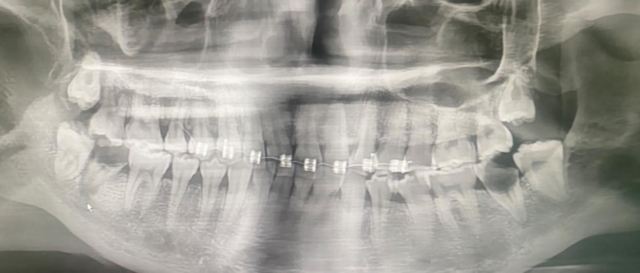

คนไข้วัยเพียง 20 ปี ตัดสินใจดัดฟันแฟชั่นกับเพื่อนในกรุงเทพฯ เพียง 6 เดือนต่อมา เริ่มมีอาการไอ หายใจลำบาก และสุดท้ายพบว่าเชื้อแบคทีเรีย Streptococcus gordonii จากการติดเชื้อในช่องปาก ได้แพร่เข้าสู่กระแสเลือด ทำให้คนไข้ป่วยเป็น “เยื่อบุหัวใจอักเสบติดเชื้อ” Infective Endocarditis จนลิ้นหัวใจรั่ว และต้องเข้ารับการผ่าตัดเปลี่ยนลิ้นหัวใจเทียม สิ่งที่เริ่มต้นจากความ "อยากสวย" จบลงด้วยการต้องพึ่งพาลิ้นหัวใจเทียมไปตลอดชีวิต สิ่งนี้คุ้มค่าที่จะแลกหรือไม่?

เคสจริงที่หมอเจอ น้องอายุเพียง 20 ปี เริ่มจาก จัดฟันแฟชั่นในกรุงเทพฯ → ฟันผุ มีหนอง

→ เชื้อเข้ากระแสเลือด → จับเชื้อ Streptococcus gordonii

→ กลายเป็น เยื่อบุหัวใจติดเชื้อ (Infective Endocarditis)

สุดท้ายลิ้นหัวใจรั่ว ต้องผ่าตัดเปลี่ยนลิ้นหัวใจ ทั้งที่ยังอายุน้อยมาก

จัดฟันแฟชั่นทำมาจาก กทม. สัก 6 เดือนที่แล้ว ไอ หายใจไม่ค่อยสะดวก โทรหาแม่ แม่เลยพามารักษาที่น่าน อายุ 20 ปี แม่ให้ลาออกจากงานมารักษาตัวให้หายก่อน